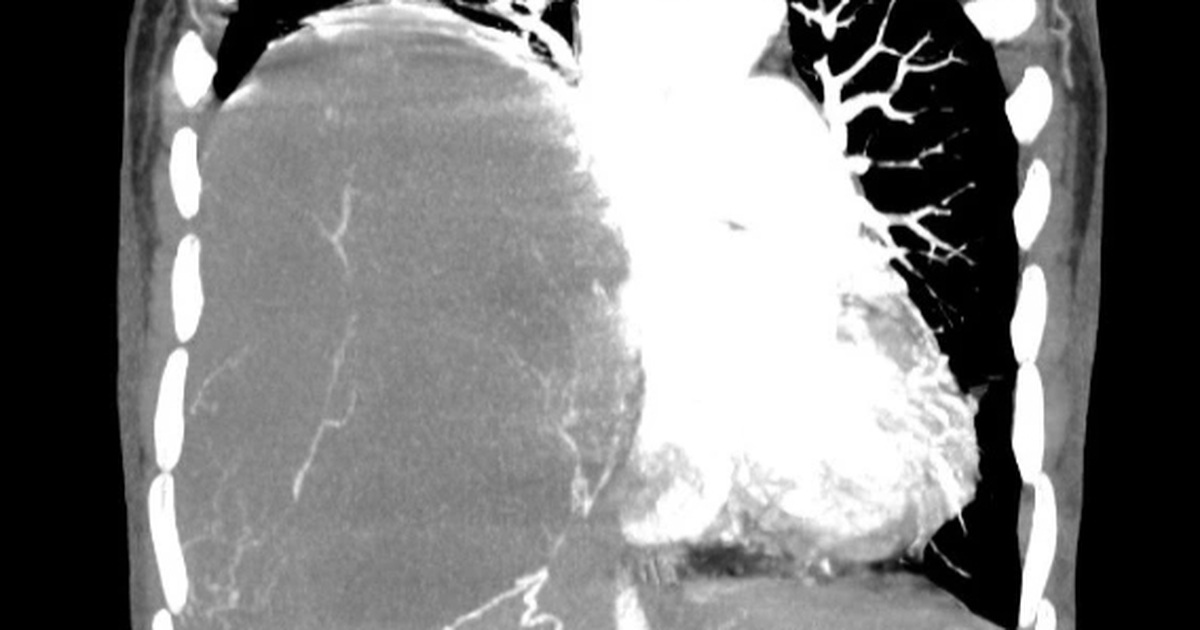

Kết quả chụp cắt lớp vi tính tại Bệnh viện Ung Bướu Hà Nội cho thấy, lồng ngực phải bệnh nhân có khối đặc kích thước 20x15cm đè xẹp phổi, thâm nhiễm trung thất, thành ngực.

Hình ảnh khối u choán hết khoang lồng ngực của bệnh nhân (Ảnh: Bệnh viện cung cấp).